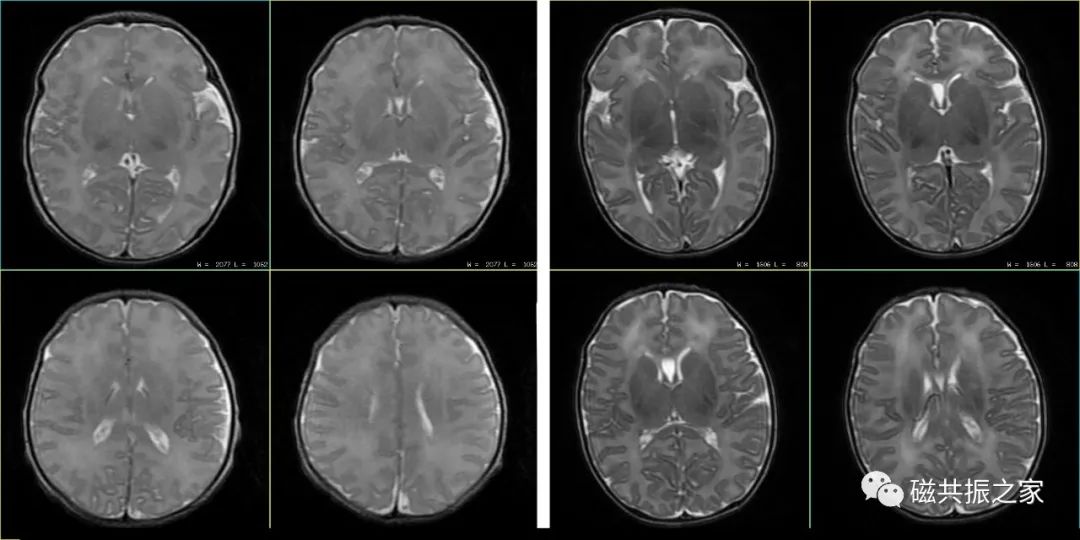

患儿4d,T2WI FSE△,1.5T。

左:TR=3100ms,TE=120ms。

右:TR=5200ms,TE=210ms。

对于婴幼儿颅脑的扫描,特别是对于小于3个月的婴儿,不管是T1WI还是T2WI,都应适当的延长TE和TR值,以获得更好的图像信噪比和对比度,且扫描参数应根据磁场及扫描目的做出相应的调整。婴幼儿随着年龄的增长TR逐渐降低,通常至2周岁时与成人TR类似。